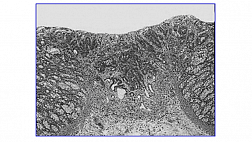

Иллюстрация №10: Рис. 10. Аденокарцинома пищеводно-желудочного перехода. Окраска Гематоксилин-Эозином, увеличение х 100. Инвазивные криброзные очаги аденокарциномы.

Морфологическое и иммуногистохимическое заключение: умеренно дифференцированная аденокарцинома пищеводно-желудочного перехода, grade II (рис. 10). Опухоль прорастает в подслизистый слой (sm3), в просветах сосудов определяются очаги опухоли (Ly «+», V «+»), в краях препарата признаков опухолевого роста не выявлено, (LM «-», VM «-»), рис. 11.